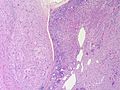

| Metastasis | sharp interface with brain, often glandular, +/-nucleoli, no glial processes | often cerebellular, well-circumscribed | usu. old | often suspected to have metastatic disease | TTF-1, CK7, CK20, BRST-2 |

Secondary

Carcinomas:

- Well-demarcated border between brain and lesion - key feature.

- No cytoplasmic processes.

- Usu. have nuclear atypia of malignancy.

- Nuclei often ~3-4x the size of a RBC.

- +/-Glandular arrangement.

- +/-Nucleoli.